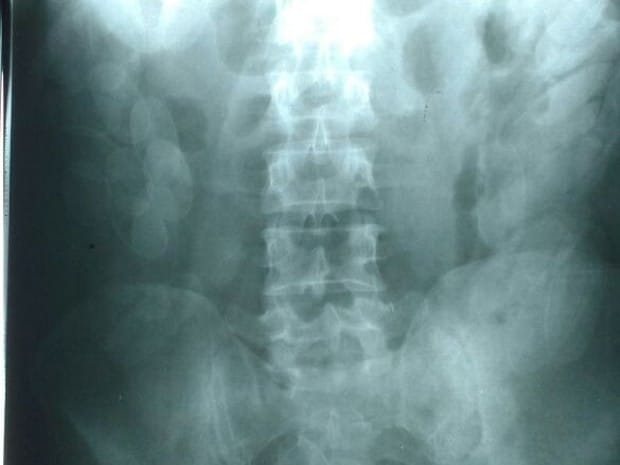

Segundo informações da Polícia Rodoviária, o ônibus foi abordado no km 433 pela força tática e os policiais desconfiaram do passageiro. O suspeito foi encaminhado para a UPA e um exame de raio-X constatou que ele havia engolido as cápsulas.